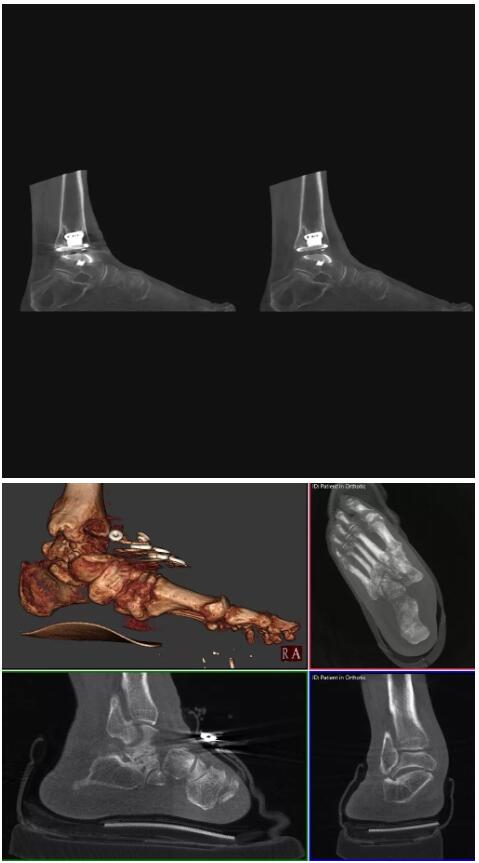

比如上面這款專用于足部和踝部掃查的CT成像系統(tǒng),患者在進(jìn)行CT掃查時只需要站在上面即可,雙腳站或者單腳站都可以,當(dāng)然,如果患者不是那么方便站著做完CT掃查,也可坐在上面。

這款CT掃查系統(tǒng)自帶屏蔽裝置,它的體積非常小,僅需要極小的空間即可,并不像常規(guī)CT那樣需要一間單獨的檢查室。此外,這種CT掃查的速度非???,僅需30秒左右可以完成檢查,輻射劑量相對常規(guī)的CT要少許多,尤其適合醫(yī)院的骨科使用。

而患者站著做足部或者踝部做CT檢查還有個好處是,可以檢查患者在負(fù)重的情況下,骨關(guān)節(jié)的真實情況,而躺著做CT掃查時未必能看出來。負(fù)重CT掃查特別是對于受傷的運(yùn)動員或者舞蹈員來說意義更大,能夠更準(zhǔn)確地評估傷情,幫助他們盡早復(fù)原。

以下是這些“特立獨行”的CT所拍出來的圖像: